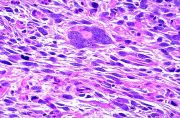

| 2021年12月10日 (五) 13:15 | 13号切片-纤维瘤-镜下观2.jpg (文件) |  |

175 KB | Cirno.9 | 基于MsUpload的文件上传 | 1 |